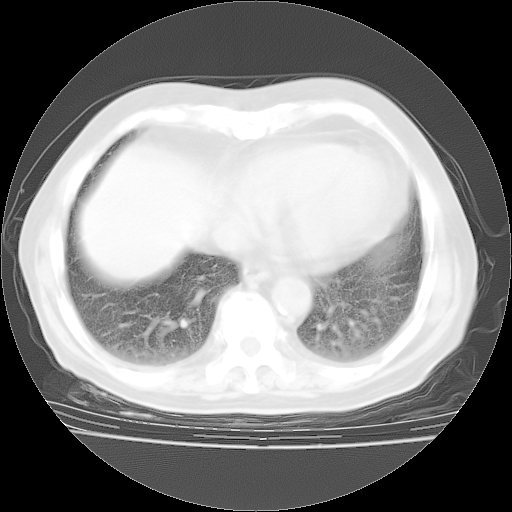

4月28日肺部CT——再次出现类似去年5月9日——透光度降低,“间质性”改变。

4月28日肺部CT——再次出现类似去年5月9日——磨玻璃样、间有“粟粒样”改变。

个人阅读4.14日肺部CT平扫:纵隔窗无异常,但肺窗示:双下肺内、后基底段有片絮状侵润影,部位以后基底段为著,以间质改变为主,呈急性肺泡炎征像,和首次住院影像学有相似之处。仅是个人读片,明日请相关专家再读片哈。其它建议同上。